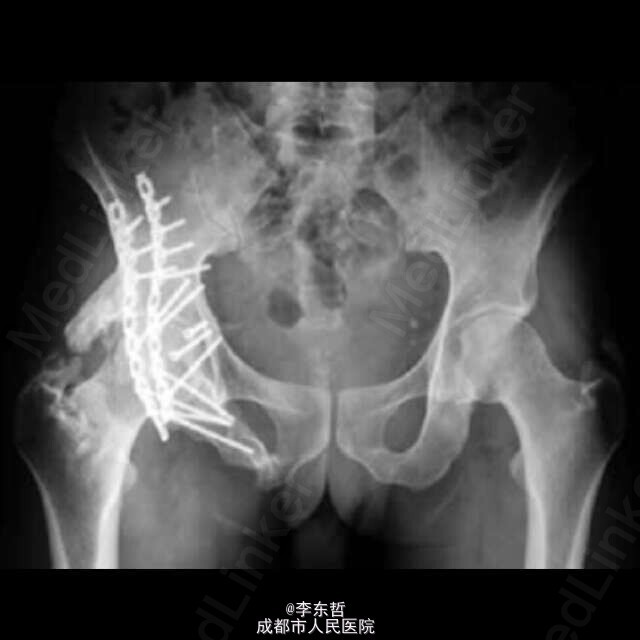

创伤性双侧不对称髋关节脱位很少见,该患者为31岁的男性,被一堵重约100公斤的墙砸伤于腰骶部,导致骨盆骨折、右髋关节后脱位及右髋臼的粉碎性骨折、左髋关节的前脱位